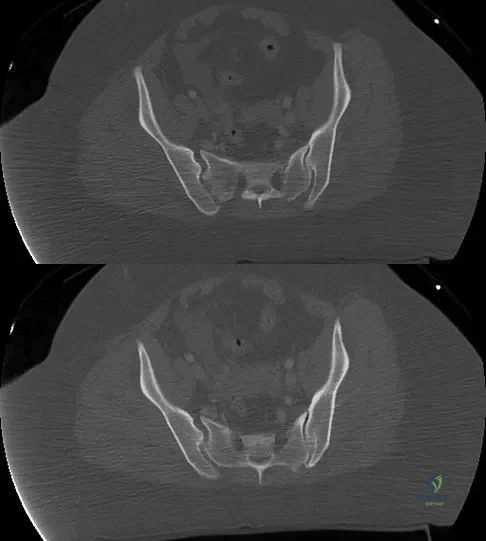

Question 87 High Yield

A 36-year-old woman was injured in a train derailment. She has a significant open depressed skull fracture with active bleeding, a hemopneumothorax, and blood in the left upper quadrant and colic gutter by Focused Assessment with Sonography for Trauma (FAST) examination. Additionally, she has the pelvic injury seen on the CT scans in Figures 18a and 18b. The mortality rate for this patient approaches

Detailed Explanation